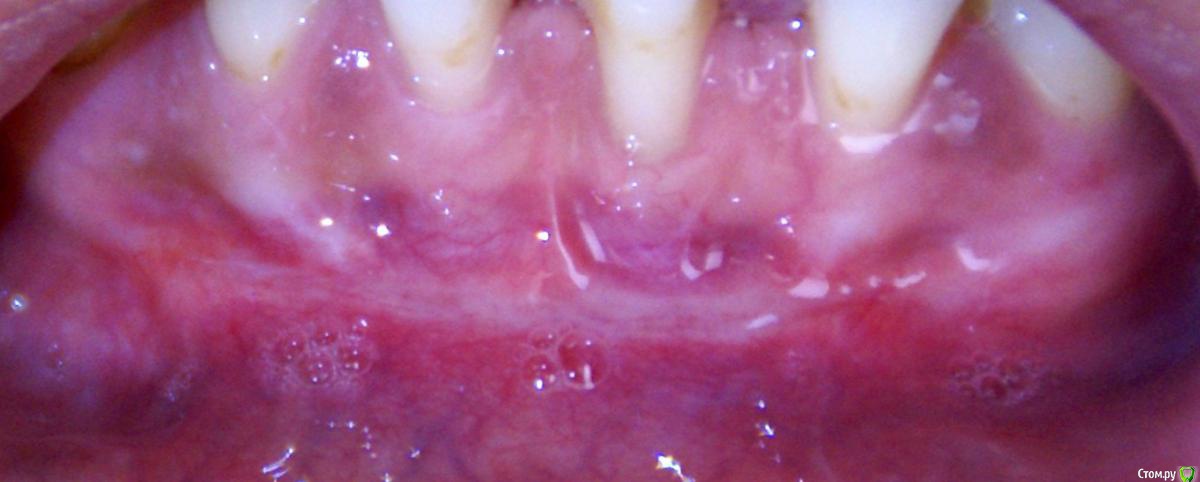

Irina_S Опубликовано 15 июня, 2017 Поделиться Опубликовано 15 июня, 2017 Здравствуйте, уважаемые специалисты! Заранее прошу прощения за не слишком качественные фото! Почти восемь месяцев назад мне была сделана вестибулопластика на нижней челюсти.За пять дней до операции ситуация во рту выглядела так: Для проведения операции были такие показания: Вот ещё описание самой операции, которая была 24 октября 2016 г.: Через шесть дней после операции: Ещё через шесть дней, 5 ноября: Прошла ещё неделя, 12 ноября: Следующий раз фото, к сожалению делалось через три с лишним недели, 4 декабря, в разных ракурсах: После этого визуальные изменения касались только уменьшения белёсых мест от разреза.Вот состояние на 10 июня этого года с разными вариантами оттягивания губы: По результатам заживления я не вижу разницы в глубине преддверия, ради чего и проводилась операция.К тому же всё время с момента операции присутствуют стягивающие ощущения и ощущение инородного тела в подбородке. Ответьте, пожалуйста, правильно ли была сделана операция вестибулопластики?Спасибо за внимание! Ссылка на комментарий

колесников Опубликовано 15 июня, 2017 Поделиться Опубликовано 15 июня, 2017 По уровню прикреплённой десны ситуация выглядит лучше,стабильнее чем до вмешательства. После вмешательств такого рода часто случаются рецидивы и неудачи,у Вас их нет. Но случаются и побочные "осложнения",в частности у Вас образовались тяжи в области клыков,которых раньше не было. Запргнозировать их оборазование зачастую невозможно. Это мягкие ткани,их можно попробовать "растянуть" или размягчить,делая миогимнастику,(надувая пузырь под губой),если это не поможет,дополнительная пластика по устранению этих тяжей. Ссылка на комментарий